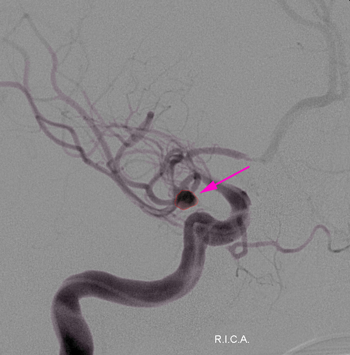

Μαγνητική, αξονική ή, κυρίως, ψηφιακή αγγειογραφία εγκεφάλου.

Η θεραπεία των ανευρυσμάτων είναι κατά κανόνα παρεμβατική με χειρουργική επέμβαση ή εμβολισμό. Η χειρουργική επέμβαση αποσκοπεί στην απομόνωση του ανευρύσματος από την υπόλοιπη αρτηριακή κυκλοφορία η οποία πραγματοποιείται με τοποθέτηση ειδικού clip στη βάση του. Ο εμβολισμός γίνεται με ενδαγγειακό καθετήρα με την βοήθεια του οποίου τοποθετούνται μεταλλικά ελάσματα εντός του ανευρύσματος με αποτέλεσμα την θρόμβωσή του.

Aneurysm1

Ανεύρυσμα (περίγραμμα)